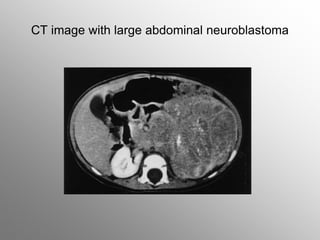

2-year-old-girl with abdominal neuroblastoma

CT image with large abdominal neuroblastoma